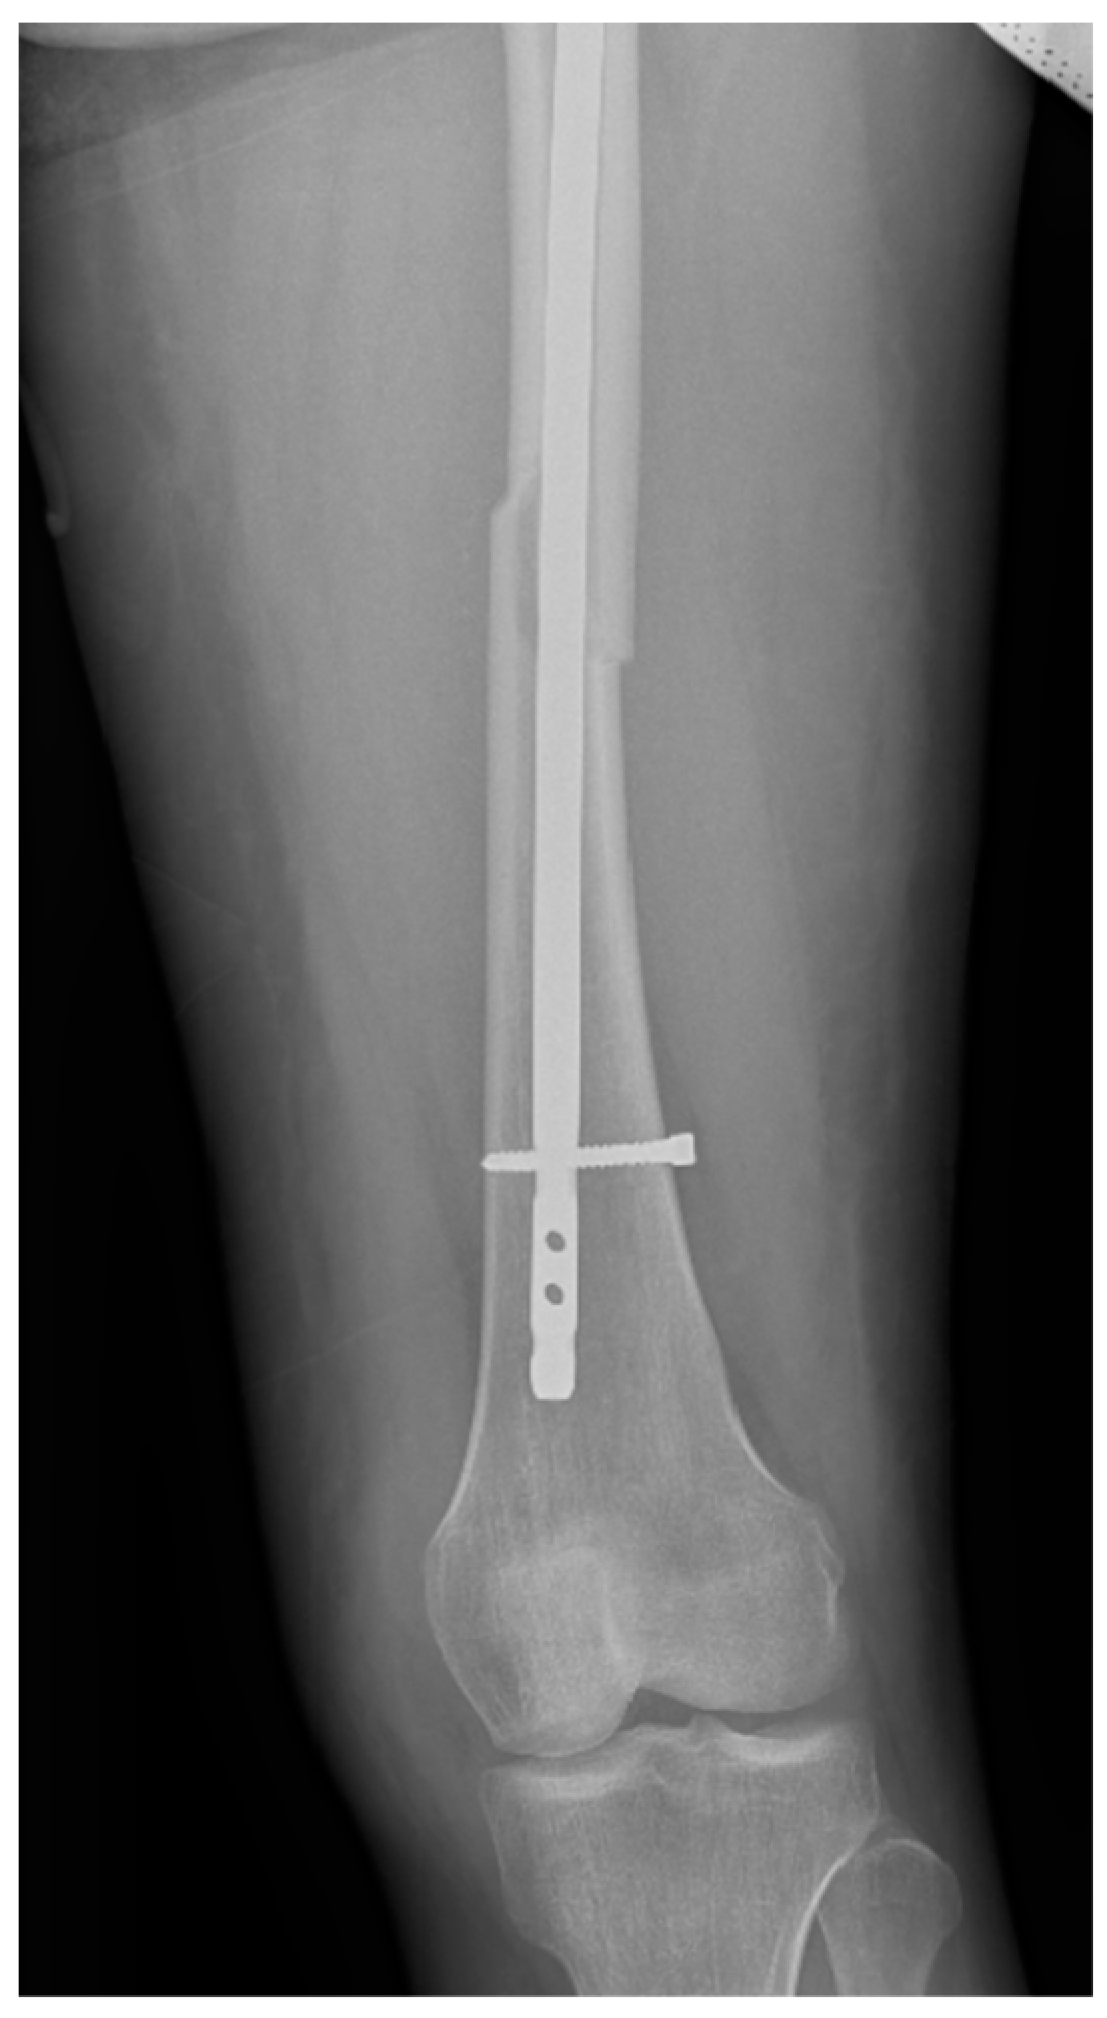

Surgical intervention was performed by a multidisciplinary team: an anesthetist, an obstetrician, a neonatologist, and an orthopedist. She underwent spinal anesthesia utilizing 0.5% bupivacaine, with the extraction of a healthy female baby, weighing 3200 g, with an Apgar score of 9 by C-section and bilateral tubal ligation at the request of the patient, followed by a successful fracture repair under intraoperative C-arm fluoroscopy. The surgical intervention for the fracture of the femur consisted of closed reduction and osteosynthesis with an anterograde intramedullary nail locked proximally and distally with a screw. The postoperative X-ray control revealed good fracture reduction and correct placement of the osteosynthesis material (Figure 2 and Figure 3).

Figure 3.

Postoperative anteroposterior view of the left thigh—distal pole of the intramedullary anterograde nail fixed statically with one screw.